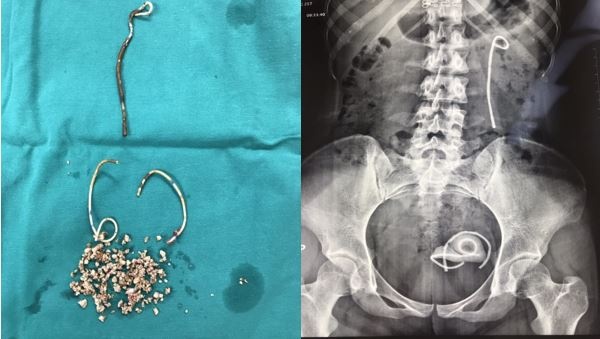

Sau khi thăm khám, các bác sĩ phát hiện niệu quản của bệnh nhân có một Stent JJ gãy thành 3 đoạn. Trong đó, một đoạn nằm trên thận, hai đoạn trong bàng quang bệnh nhân. Xung quanh Stent JJ gãy có rất nhiều sỏi bám là nguyên nhân gây đau buốt và tiểu rắt. Sỏi bàng quang của bệnh nhân có kích thước lớn hơn 3 cm.

| Sỏi được lấy ra và Stent JJ gãy thành 3 đoạn. Ảnh: BVCC |

Bệnh nhân 25 tuổi được các bác sĩ tiến hành phẫu thuật bằng phương pháp nội soi lấy sỏi qua da. Sau phẫu thuật một tuần, bệnh nhân đã ổn định và ra viện.